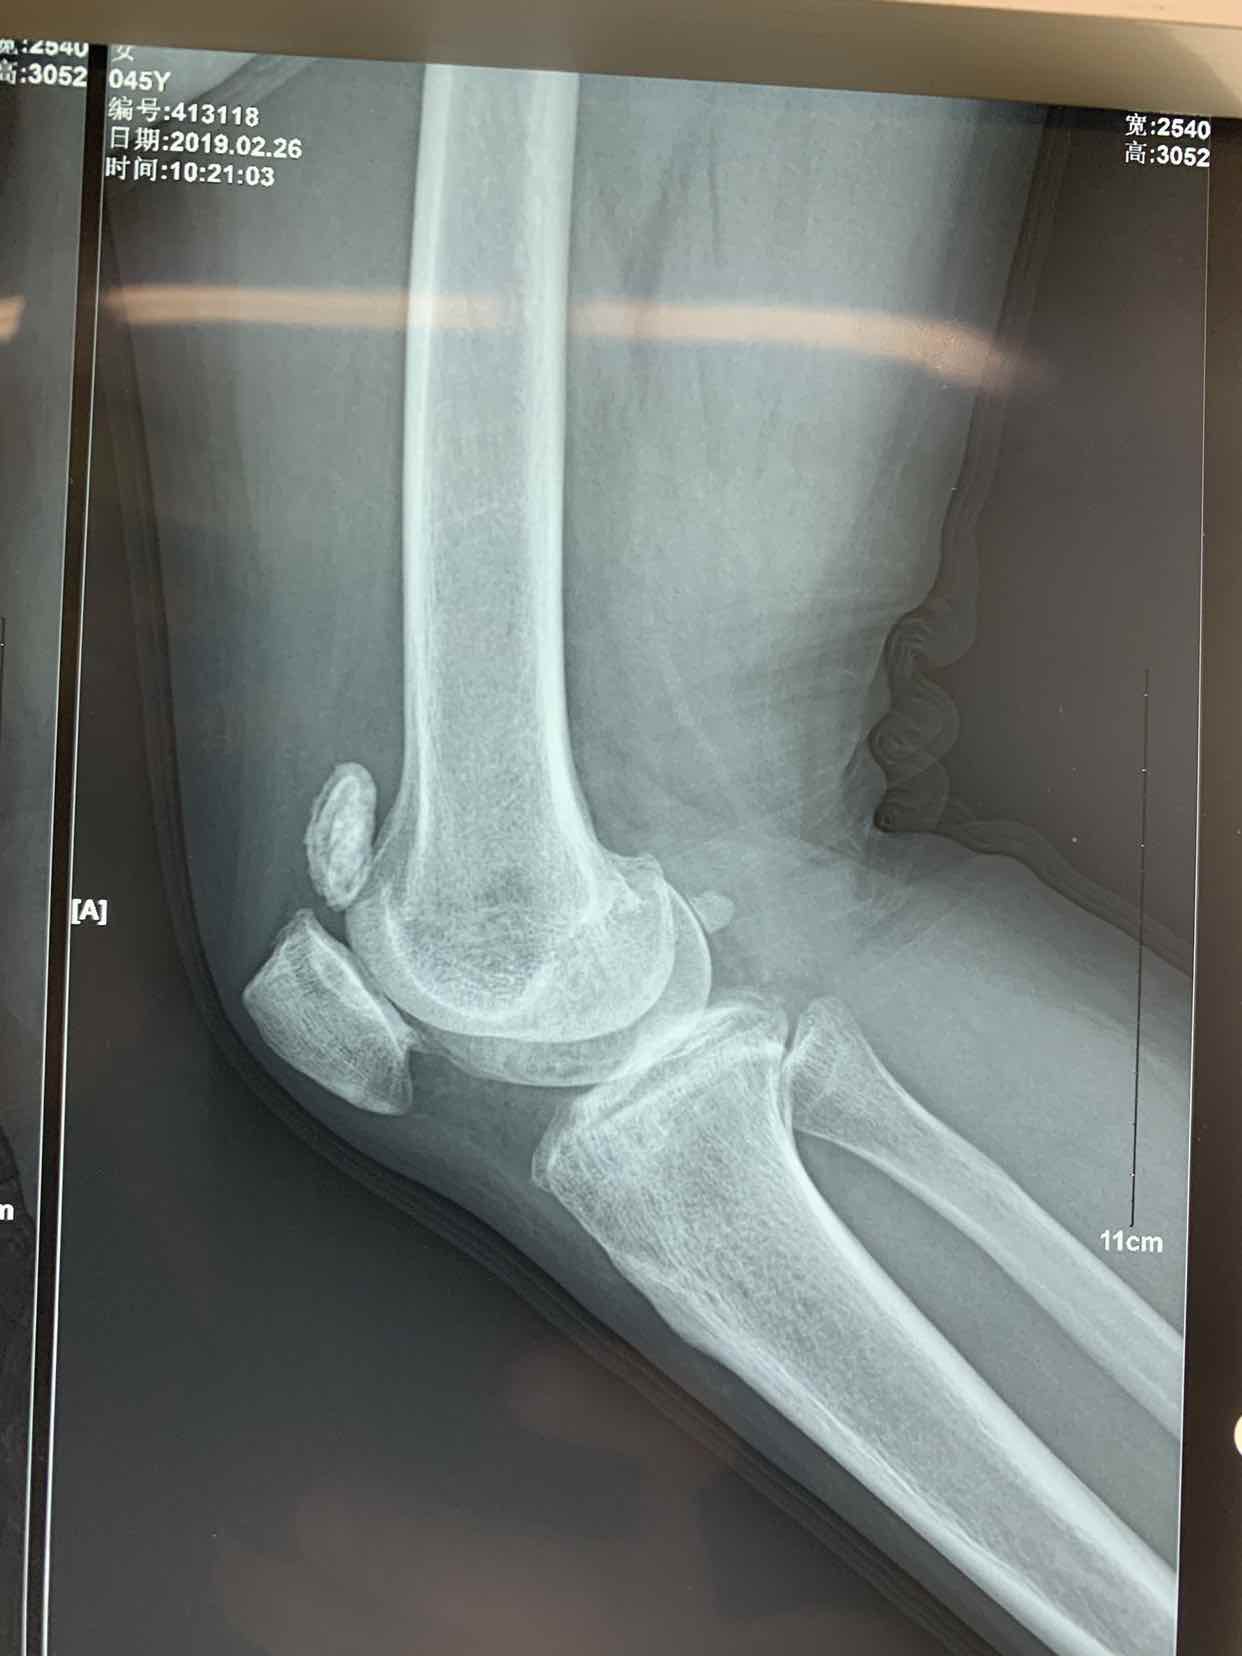

患者因双侧膝关节骨性肿物发现二十余年。收入院。患者无二十余年前无明显诱因发现双侧膝关节内有骨性肿物。异常活动。偶尔在屈曲活动时出现局部嵌夹于关节内。疼痛。不能活动。并弹响。近半年内肿物增大。疼痛发作频繁。遂来诊。门诊拍片提示见双侧膝关节内骨性游离体,位于关节内。门诊以双侧膝关节游离体收入院。

查体见患者双侧膝关节局部肿胀。压痛。可于局部触及骨性肿物在关节内游走。屈伸活动时偶有嵌顿。行走活动受限。拍片提示双侧膝关节骨性游离体。

诊断为双侧膝关节游离体。再局麻下银行膝部游离体取出术。术后患者恢复良好。

膝关节游离体是临床常见疾病。可以通过关节镜探查发作。拍片或者核磁共振检查也可获得可靠诊断。处理非常简单。发现肿物挤压至一侧。切口就可以取出。